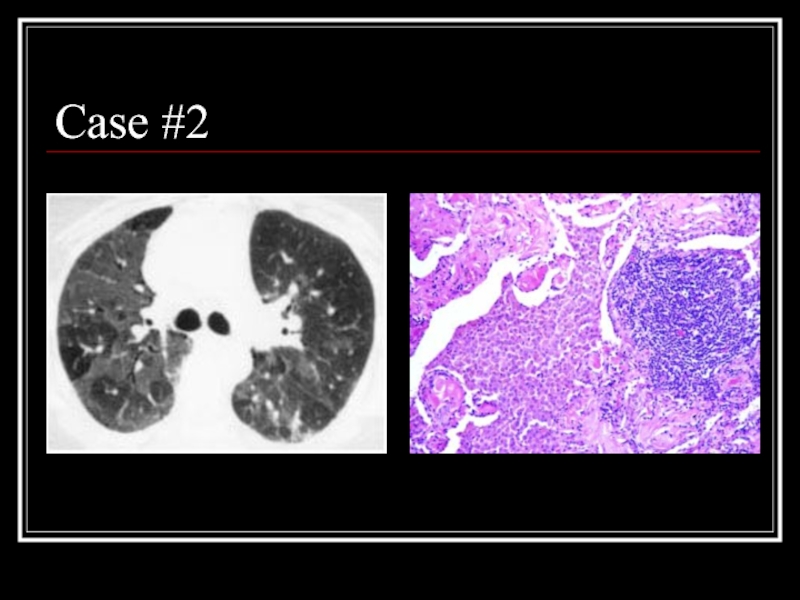

Слайд 21Case #2

Слайд 22Answer: DIP

CT: Mosaic ground-glass opacity with vascular definition in the areas

of ground-glass opacity and lobular sparing

Path: large numbers of slightly-eosinophilic staining macrophages with interstitial lymphoid aggregates